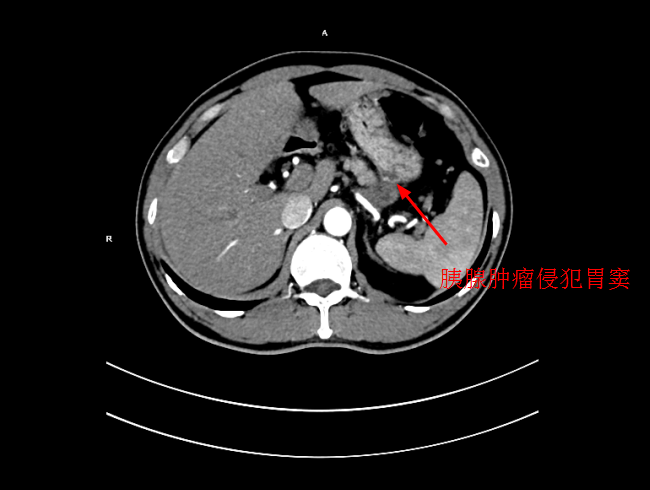

患者陳某,男,49歲,2個月前出現中上腹隐痛不适,伴有腰背部疼痛,在當地醫院就診,考慮爲胃窦炎、胃窦黃斑瘤,治療後症狀未見好轉,遂來我院就診。經過檢查後,确診爲局部晚期胰腺癌,大小爲5*3cm,癌細胞已侵犯胃窦。考慮到傳統化療方式,藥物經身體多重代謝後,到達胰腺的濃度低,達不到很好殺滅腫瘤組織的效果,且對正常組織具有一定的毒副作用。爲此李旭丹主任決定給予采用DSA下介入灌注化療,得到患者及其家屬的支持。

4月30日下午,李旭丹主任與胡志華主任上台實施介入化療術,在DSA造影下,清晰可見胰腺腫瘤的供血動脈,專家們将微導管經股動脈穿刺送達瘤體的供血動脈,成功将化療藥物灌注至瘤體,順利完成手術。術後,患者症狀明顯好轉,并于5月4日順利出院。

李旭丹主任介紹,介入灌注化療,因其能準确定位腫瘤供血動脈,将藥物直接送達瘤體,能更好殺滅癌細胞,且副作用小,在胰腺癌的治療中有着非常明顯的優勢,能爲患者赢得更多的生存機會。